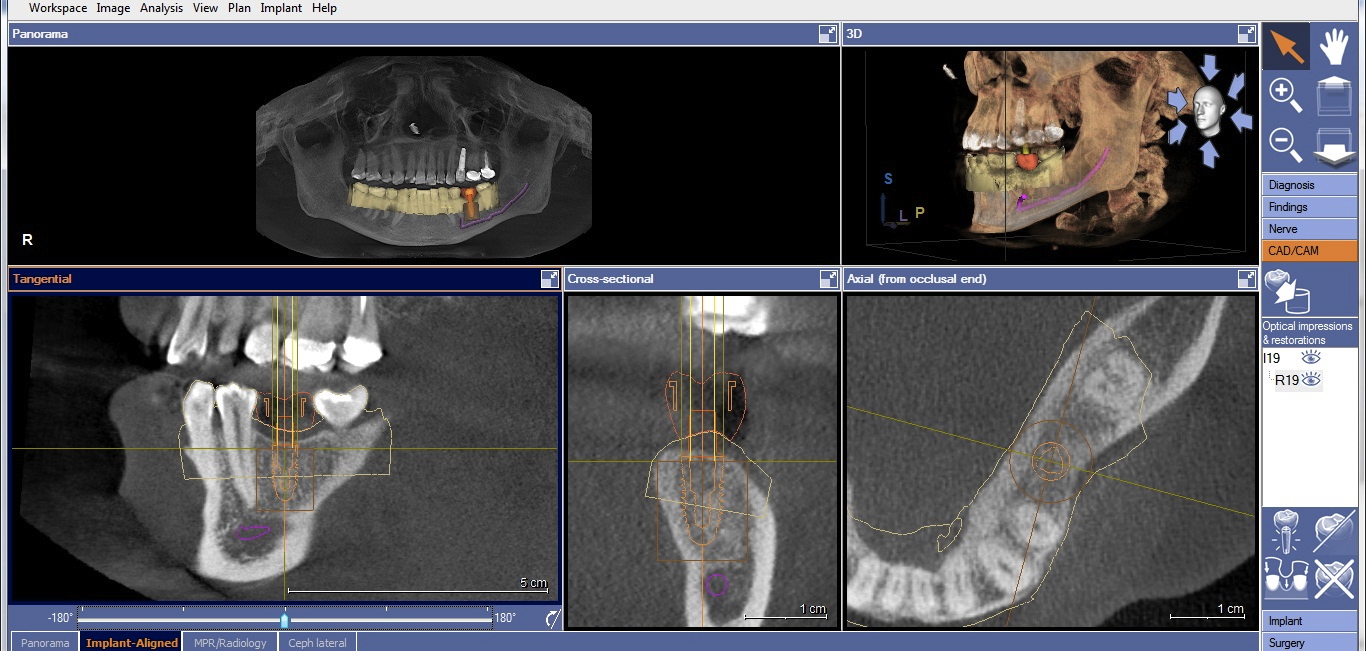

Once the desired restorative outcome is in a digital format, the patient’s CBCT scan is opened in the implant-planning software. If the edentulous space is in the posterior mandible, the inferior alveolar nerve bundle (IANB) is traced so that it is highlighted and avoided by the planned implant (Figure 2). Now, the patient’s digital restoration can be imported. Once imported, most software requires the user to identify corresponding landmarks on the digitized model and on the CBCT to merge the two data sets. It is best to avoid using teeth with crowns or large restorations as landmarks, because they cause distortions in CBCT scans and may result in inaccuracies in data set merges. Once complete, merge accuracy is verified by the user and is either confirmed or reset.

Cone-beam computed tomography (CBCT) with traced and highlighted inferior alveolar nerve bundle (IANB).

Figure 2

CBCT with final implant plan. Note the digital restoration, TiBase abutment, and highlighted IANB.

Figure 3